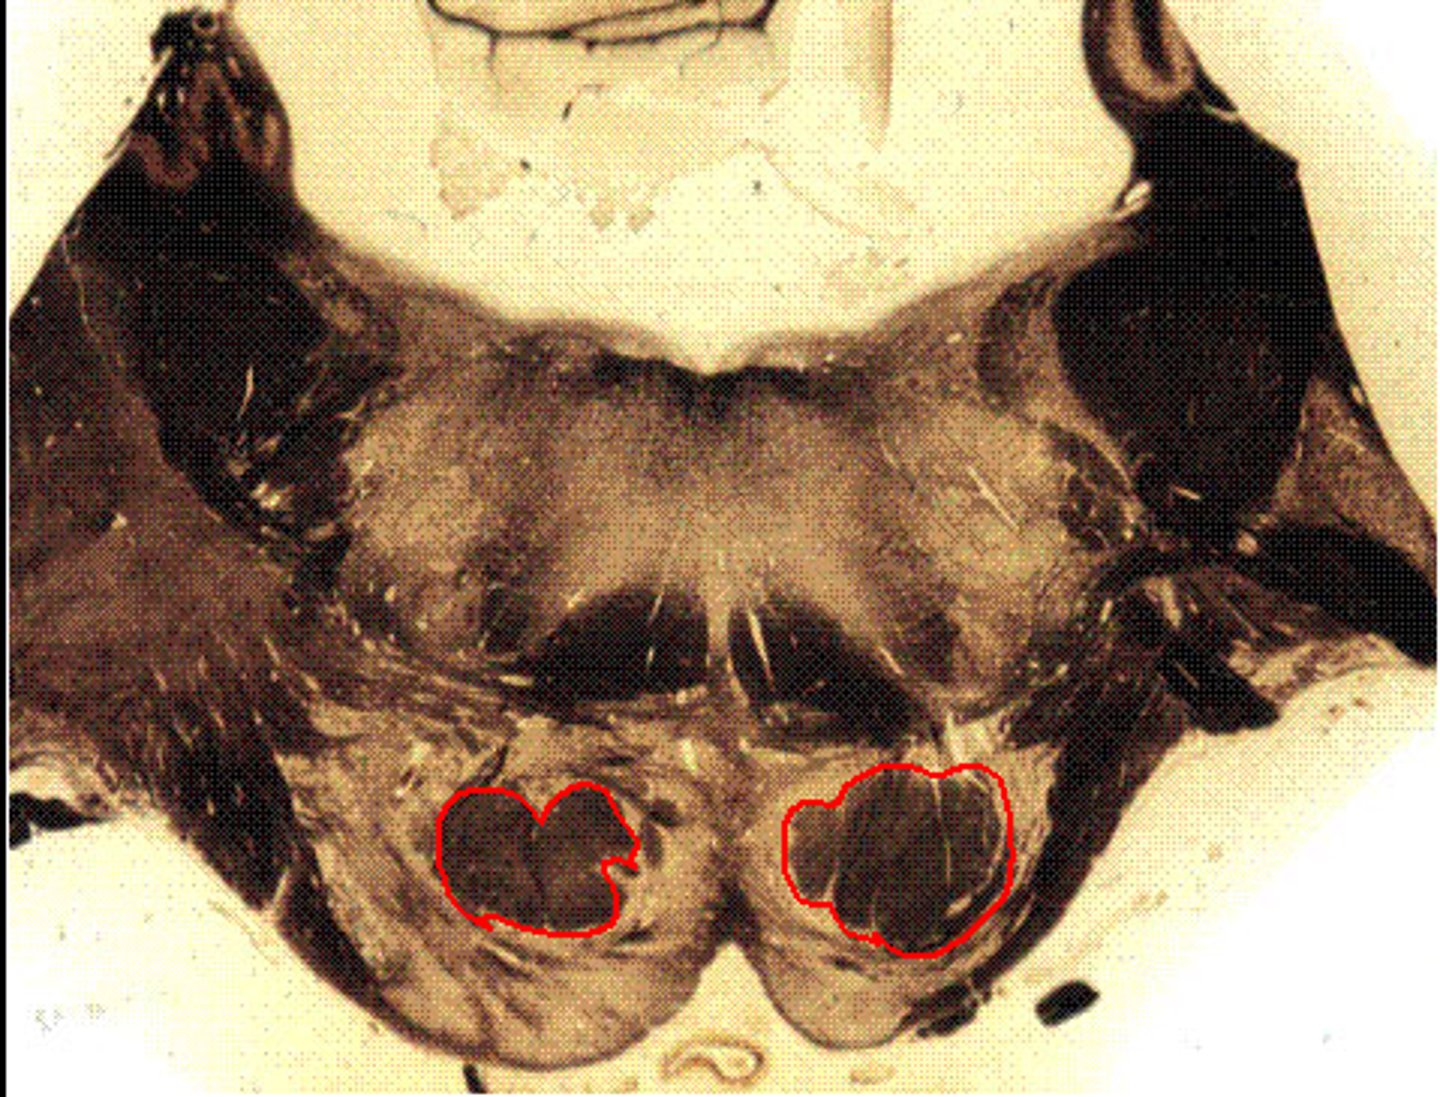

Deep cerebellar nuclei

Deep cerebellar nuclei were not included in brainstorm schematics, note where these are

Pons Trigeminal Nuclei

Fourth Ventricle

Superior Cerebellar Peduncle

Reticular Formation

Medial Lemniscus

Pontine Nuclei

Transverse pontine fibers

also called pontocerebellar fibers

Corticospinal Tract

Corticobulbar and Corticopontine fibers are also in this area